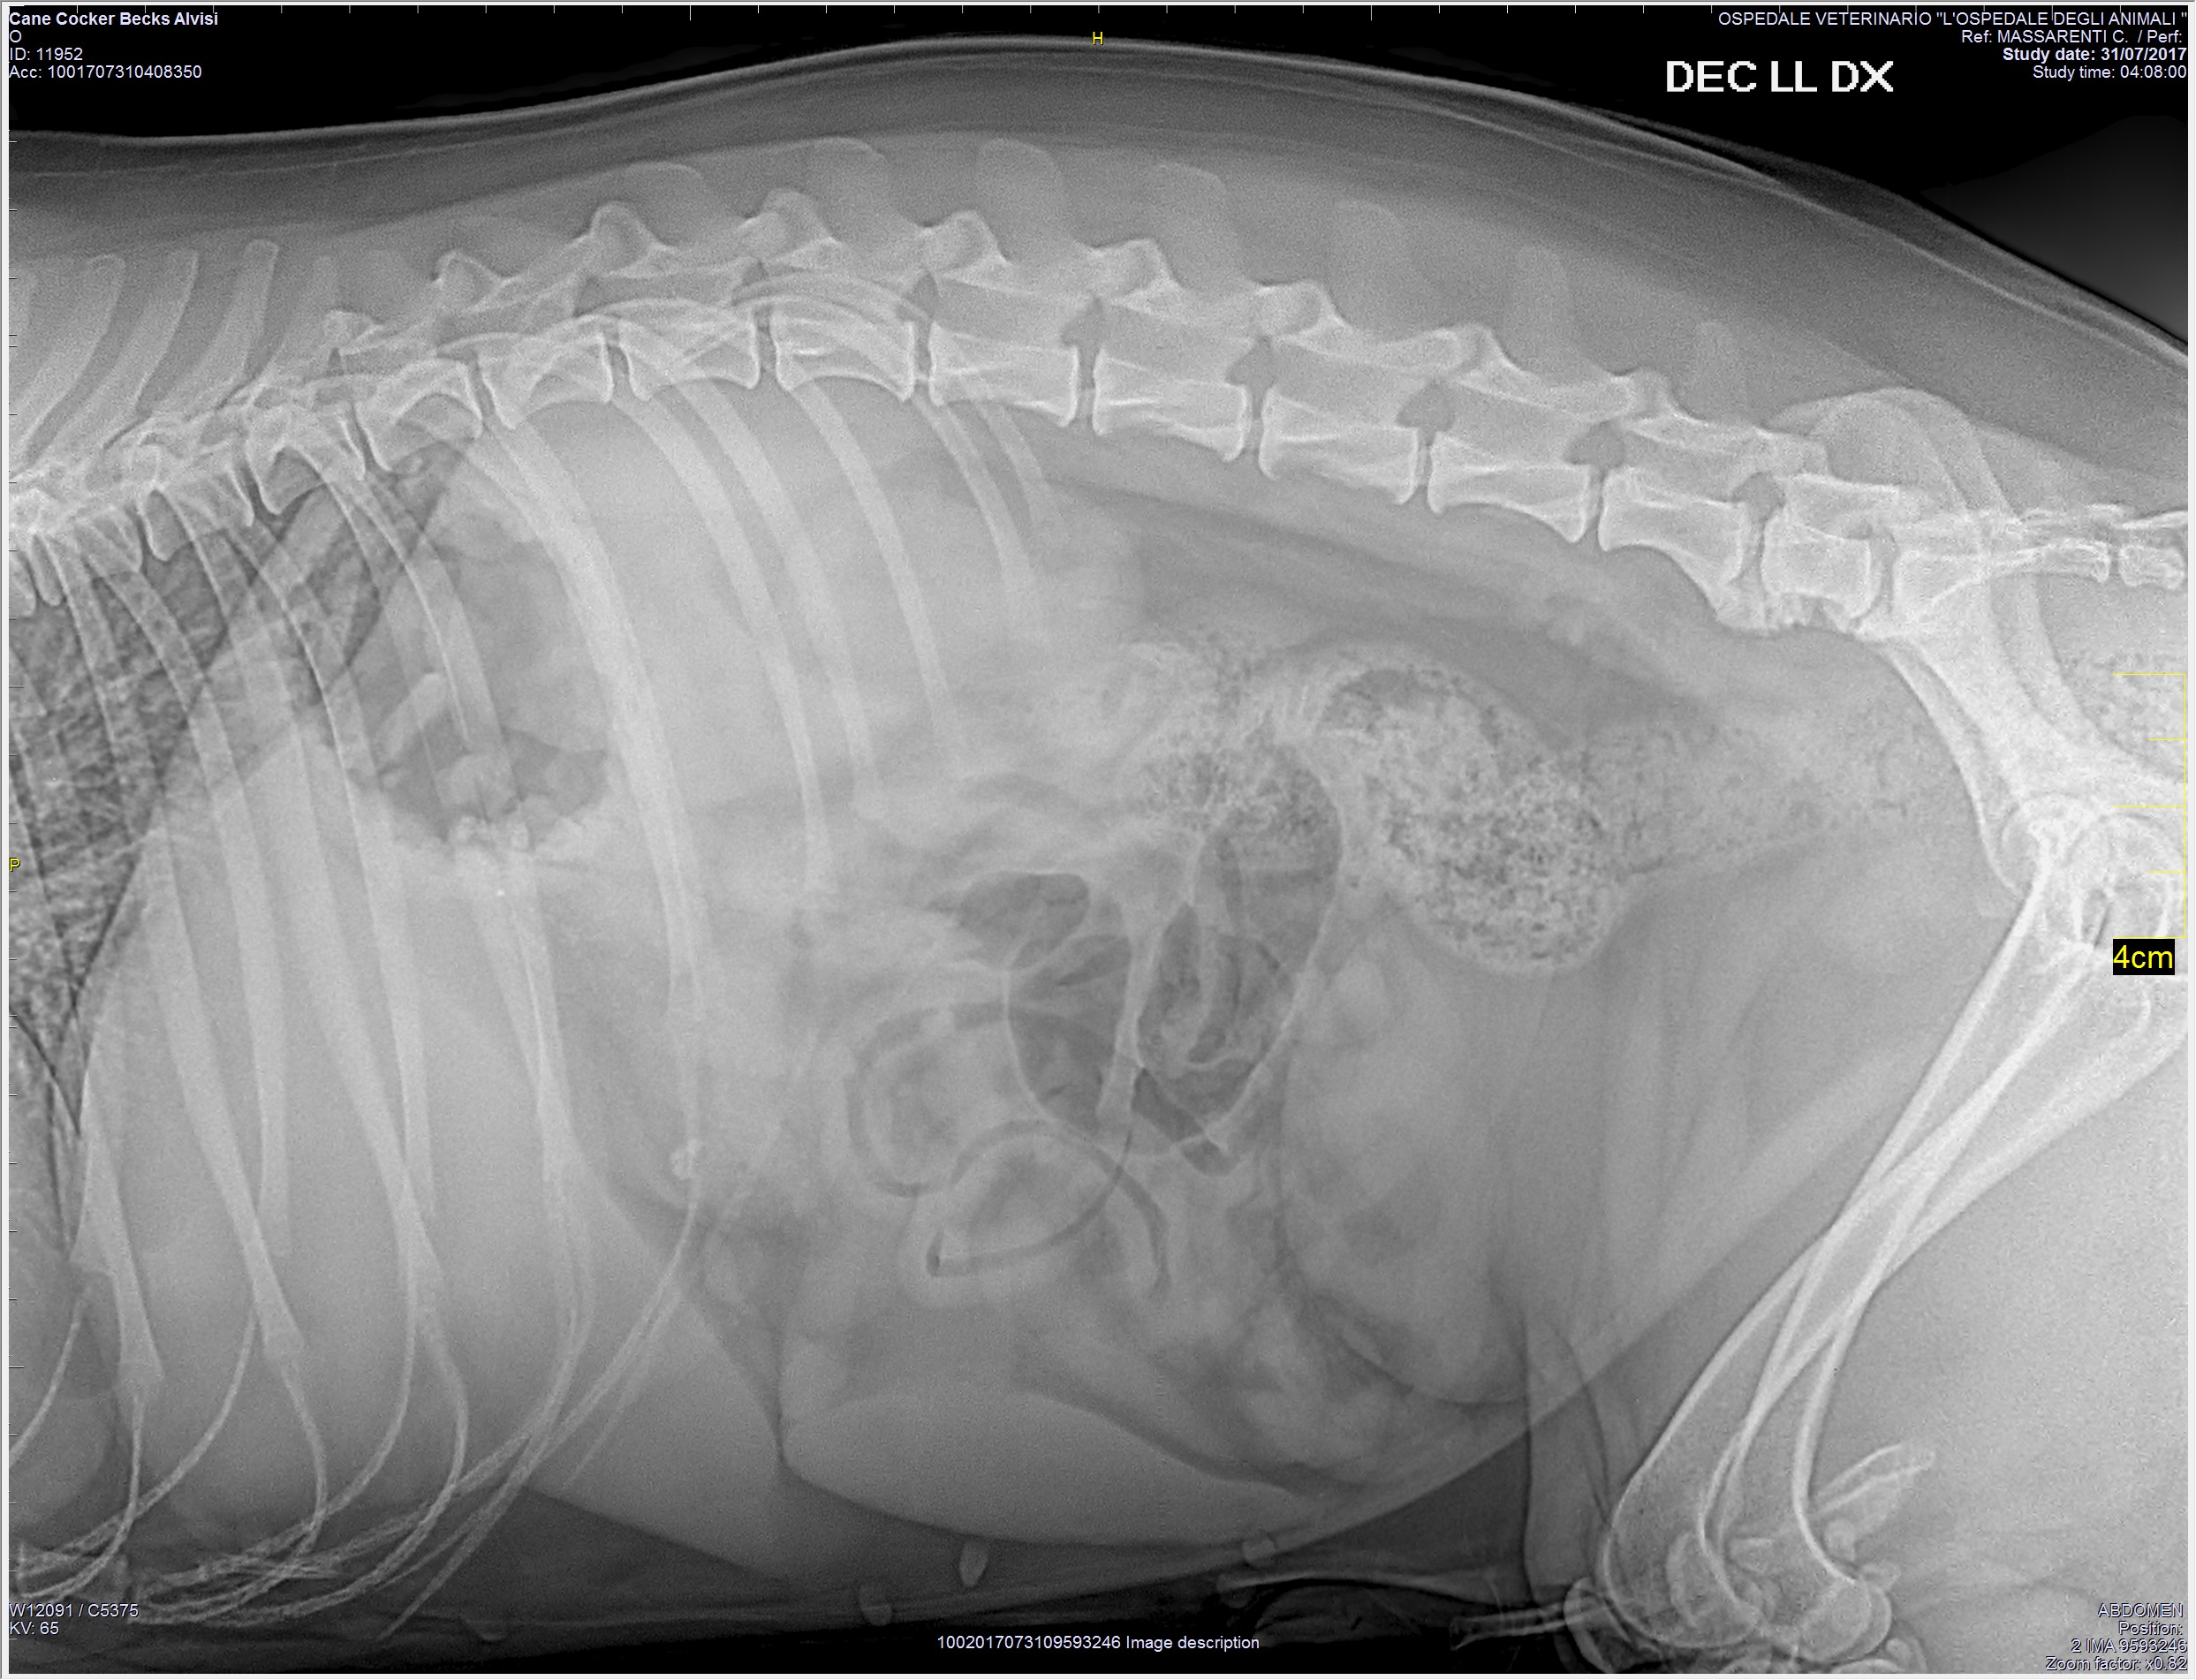

RADIOLOGIA

La radiologia veterinaria è una branca della diagnostica per immagini che utilizza i raggi-x per la valutazione delle diverse strutture anatomiche. L' Ospedale degli Animali dispone di un apparecchio radiologico digitale diretto, che permette di ottenere rapidamente radiografie di altissima qualità ed è in grado di eseguire studi radiografici di routine e d'urgenza, 24 ore su 24.

L'Ospedale degli Animali è abilitato ad eseguire studi radiografici specifici per le patologie congenite di anche e gomiti, ai fini della valutazione FSA.

Al termine dell'esame le immagini vengono digitalizzate su un cd-rom che resta a disposizione del proprietario o inviate al suo indirizzo e-mail.